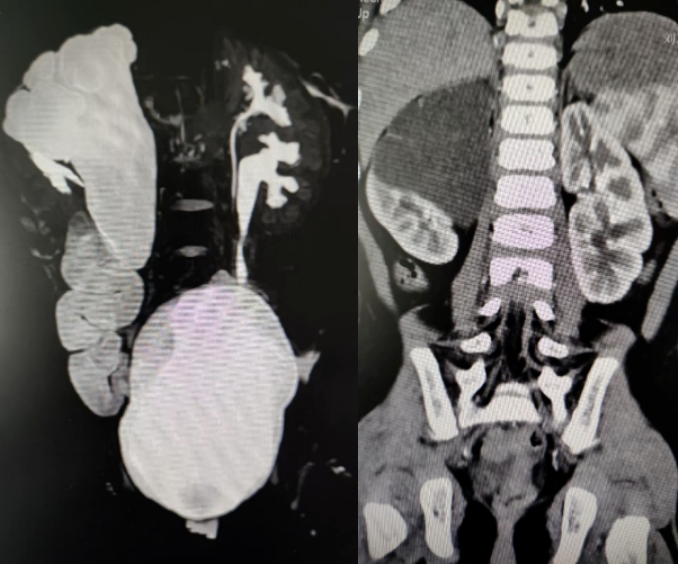

患兒CT影像表現(xiàn)

就像星月,她患側重復腎的上半腎已喪失功能,且腎盂輸尿管全程擴張,這才導致了反復感染,必須進行手術切除病變部分。